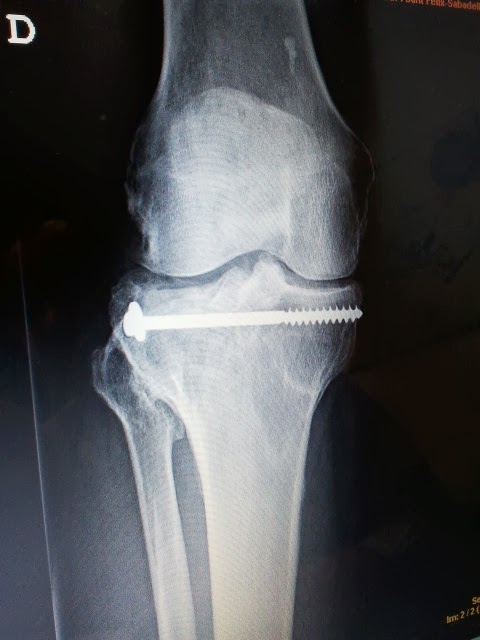

Los implantes de oro periarticulares pueden colocarse tanto en artrosis primaria como secundaria. En este caso se colocaron en una gonartrosis secundaria a fractura por accidente de moto. El resultado postoperatorio inmediato ha sido excelente, y luego de tres semanas de la intervención, el paciente refiere una recuperación sintomática importante, con ausencia de claudicación de la marcha y progresiva ganancia de la movilidad articular. Es manifiesto el grado de satisfacción por parte del paciente.

En las imágenes pueden observarse la Rx, el momento de la colocación de un implante, y el postoperatorio inmediato tras la colocación de los implantes de oro.